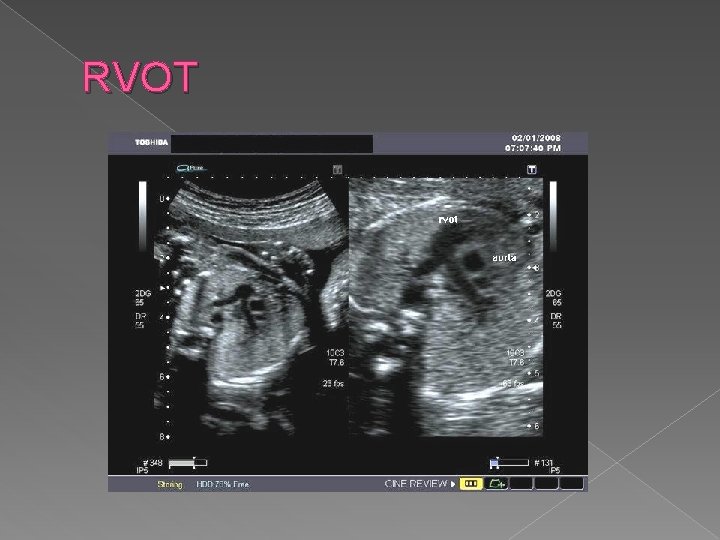

Right ventricular outflow tract view (RVOT) › ID the origin of pulmonary trunk from the right ventricle › Correct orientation of pulmonary trunk is draping anterior to the aorta when seen in cross section. › Diameter of the pulmonary artery is 9% larger than that of the aorta

RVOT